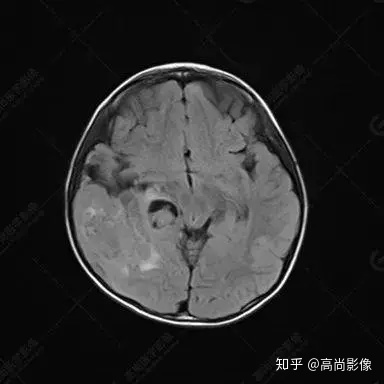

右側(cè)顳葉腫瘤切除術(shù)后(具體不詳):右側(cè)顳部骨質(zhì)不連續(xù)呈術(shù)后改變,右側(cè)顳葉術(shù)區(qū)見片狀長(zhǎng)T1長(zhǎng)T2信號(hào)影,F(xiàn)LAIR呈低信號(hào);術(shù)區(qū)后方右側(cè)顳枕葉見一巨大占位性病變影,邊界欠清,大小約6.2×5.8×4.3cm(前后×左右×上下),信號(hào)不均勻,T1WI呈等稍低信號(hào)間雜少許高信號(hào),T2WI呈高稍低混雜信號(hào),DWI示部分病灶彌散受限,相應(yīng)ADC圖減低,磁敏感序列見部分呈極低信號(hào),增強(qiáng)掃描可見明顯不均勻強(qiáng)化,鄰近硬腦膜及小腦幕增厚并明顯強(qiáng)化;另延髓右前方及右側(cè)橋小腦角區(qū)見一不規(guī)則形異常信號(hào)影,大小約3.2×1.3×3.7cm(左右×前后×上下),呈長(zhǎng)T1稍長(zhǎng)T2信號(hào),F(xiàn)LAIR呈等信號(hào),DWI未見受限,增強(qiáng)后明顯均勻強(qiáng)化,鄰近腦膜明顯強(qiáng)化。鄰近腦實(shí)質(zhì)及右側(cè)顳角明顯受壓;左側(cè)大腦半球未見局灶性信號(hào)異常,中線結(jié)構(gòu)稍左移。

右側(cè)顳葉腫瘤切除術(shù)后:現(xiàn)術(shù)區(qū)后方右側(cè)顳枕葉及延髓右前方占位,右側(cè)顳枕部硬腦膜及小腦幕明顯強(qiáng)化,結(jié)合既往影像資料,考慮為胚胎源性惡性腫瘤,如非典型畸胎樣/橫紋肌樣瘤(AT/RT)或原始神經(jīng)外胚層腫瘤(PNET)。